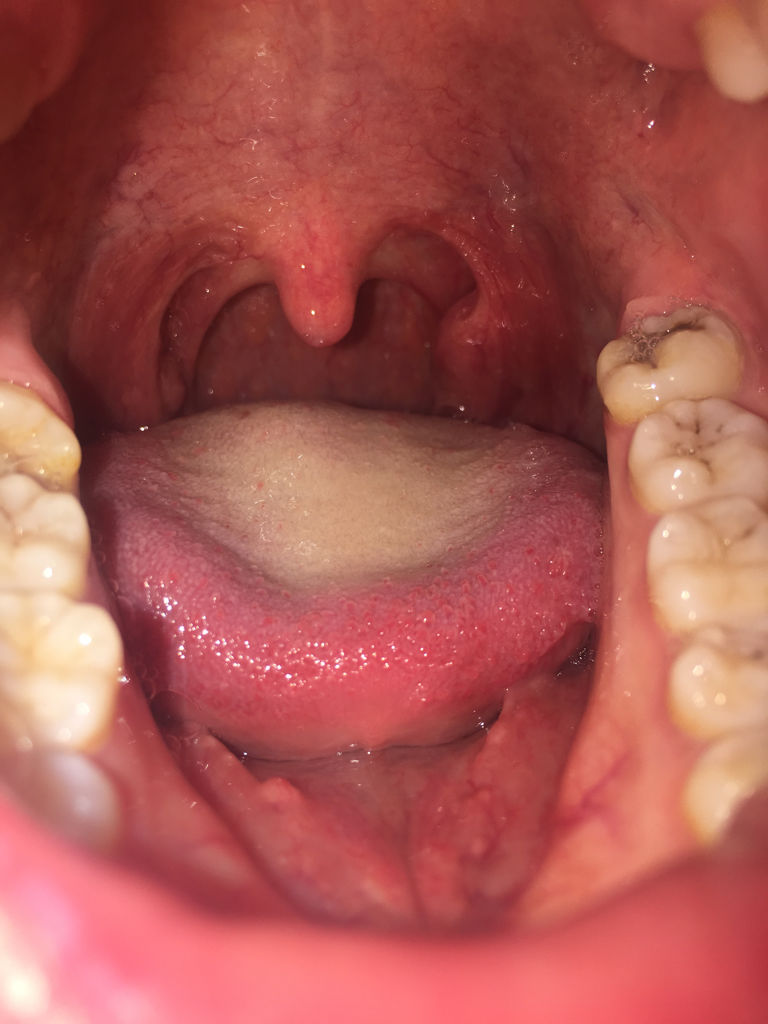

问:急性咽炎,怎么治疗,悬雍垂水肿

男孩六周岁,镜下所见,悬雍垂水肿,咽部粘膜充血,咽后壁淋巴滤泡增生

悬雍垂过长症的检查